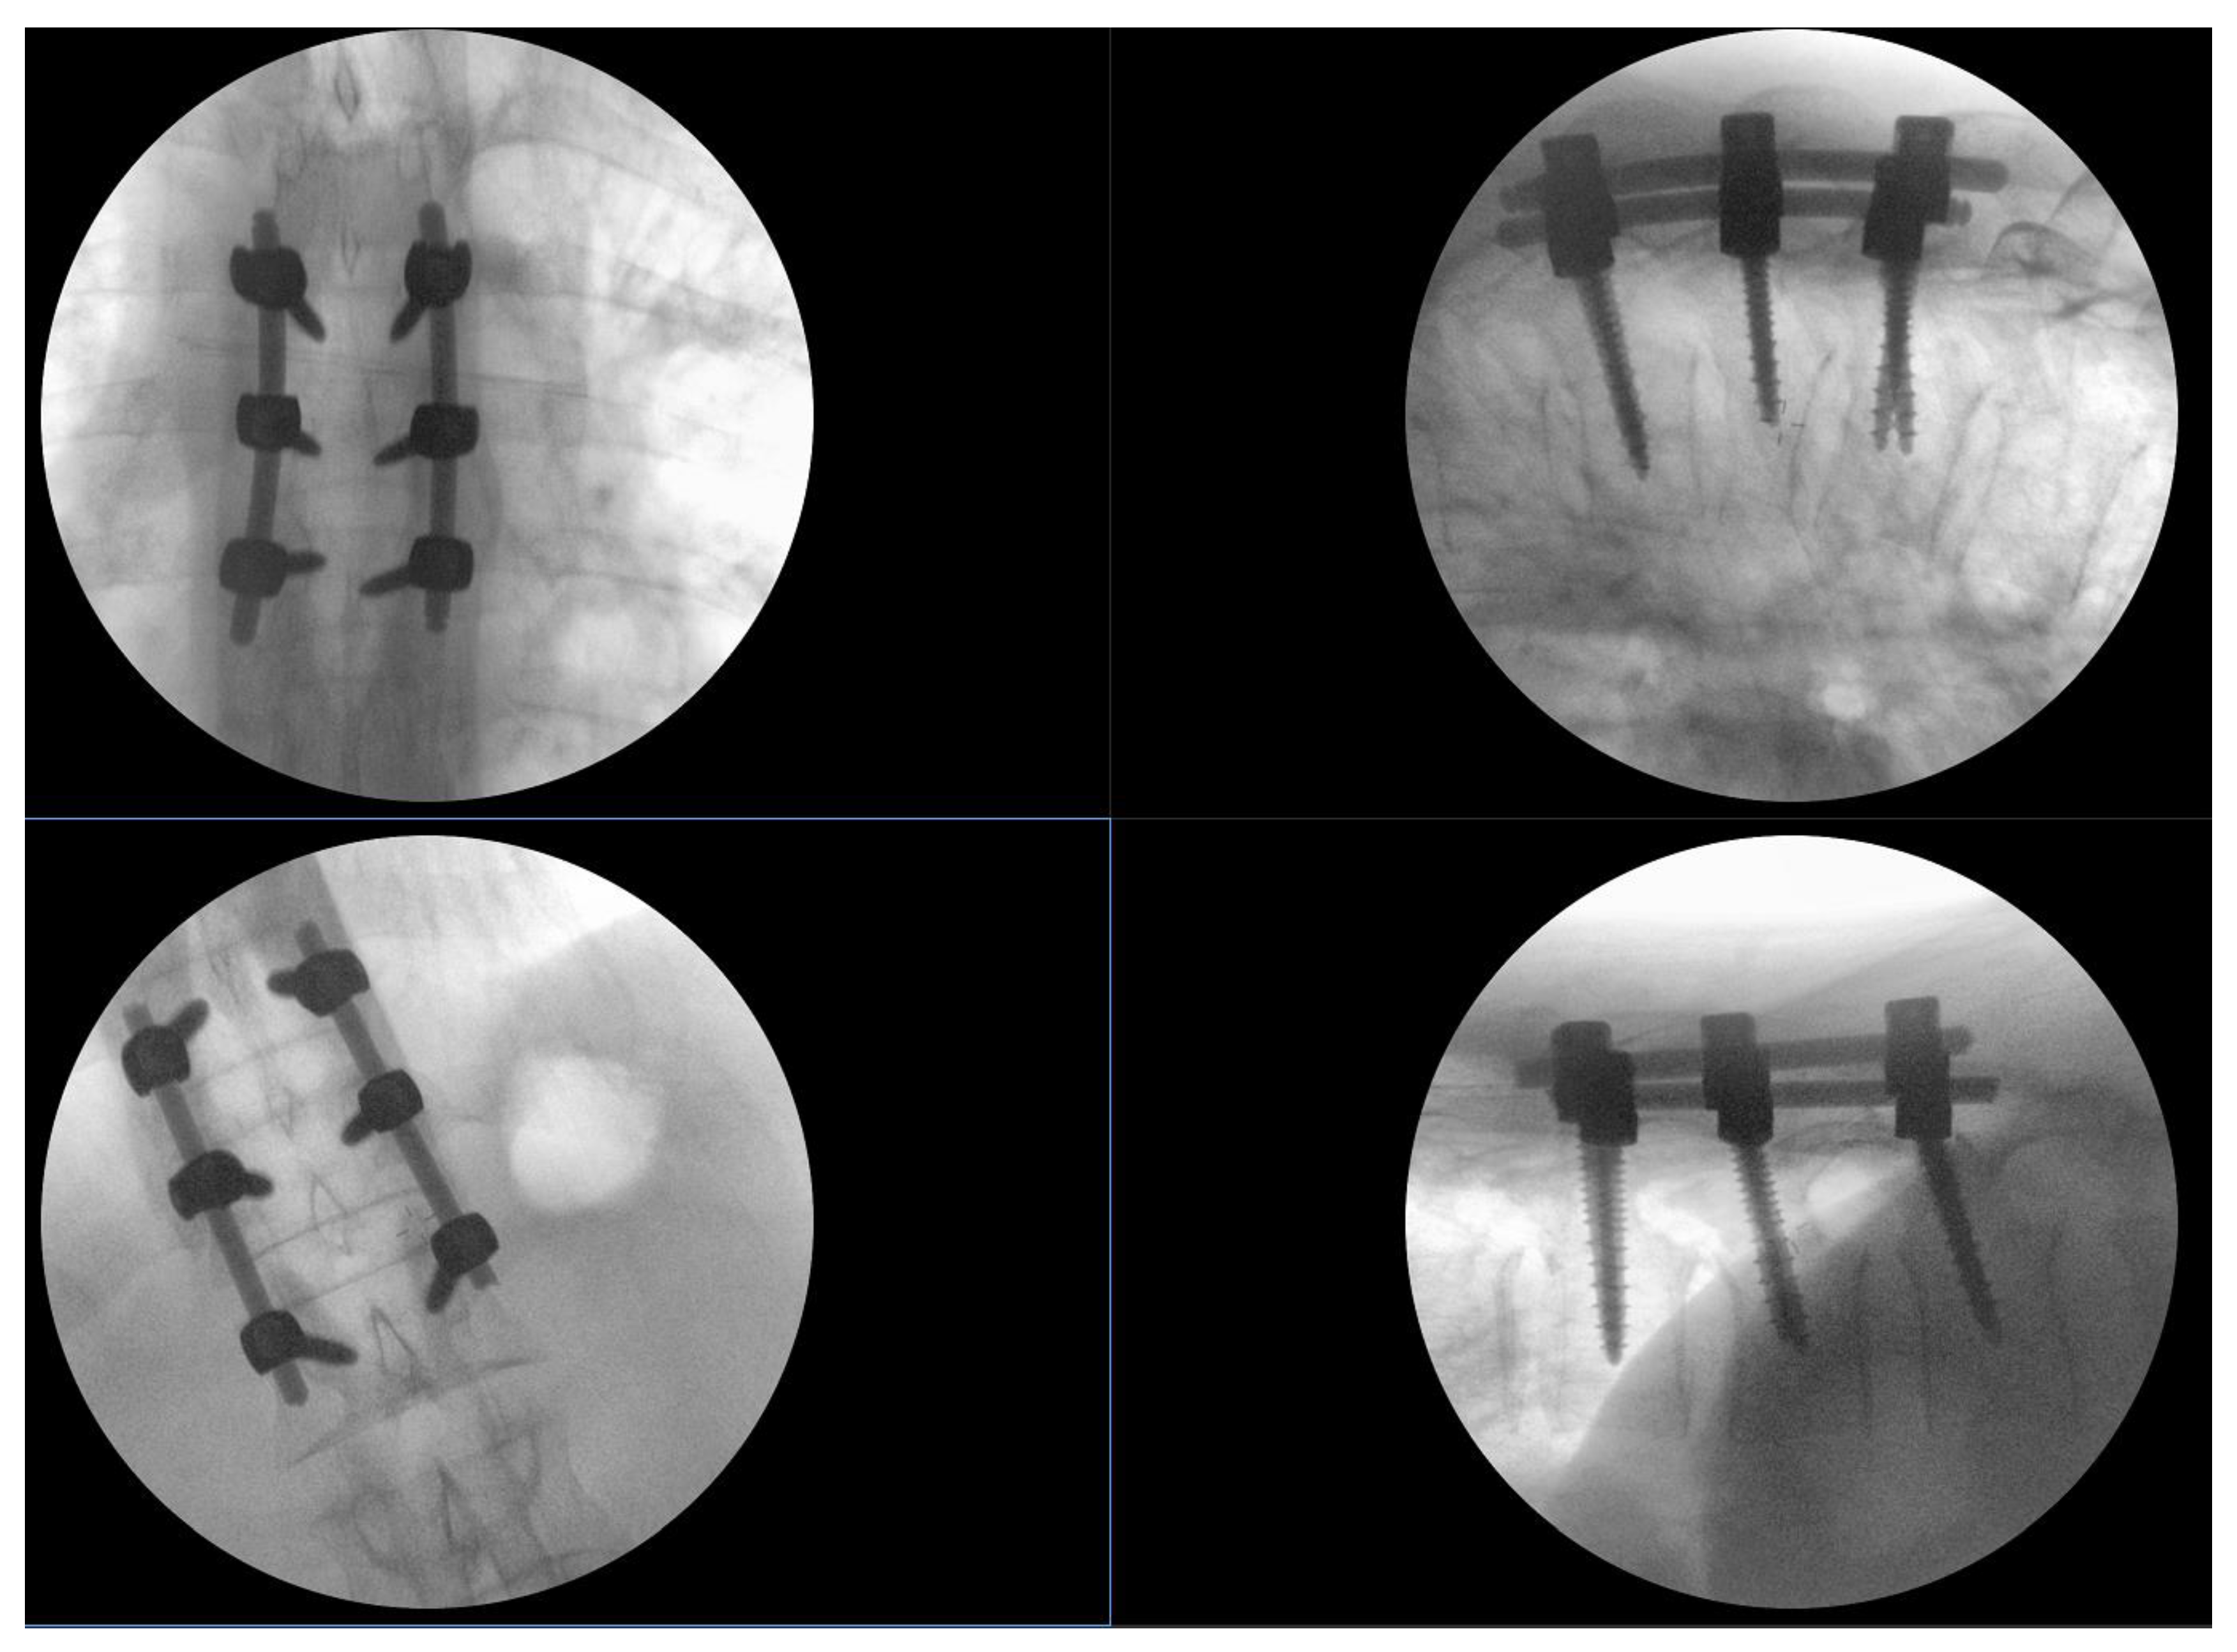

On awakening from general anesthesia, the initial postoperative neurological state was without any impairment, and he was able to urinate spontaneously. Approximately 45 minutes after surgery, he began to develop signs of hypesthesia in the lower extremities, weakness in the legs, an unsettling sensation in the abdomen, and was covered with cold sweat. Due to neurological worsening, an emergency MRI of the thoracic spine was performed, which revealed a hyperacute epidural hematoma that developed at the level of the Th6 fracture and spread cranially to Th4 as shown in Figure 3. The width was measured at 7mm and compressed the spinal cord against the laminae as shown in Figure 4. Most likely the bleeding occurred from the fracture itself.

Figure 4. Emergency T2 weighted MRI image, axial view at the Th5 level, revealing hyperacute hematoma development anterior to the spinal cord and causing significant dorsal displacement and compression.